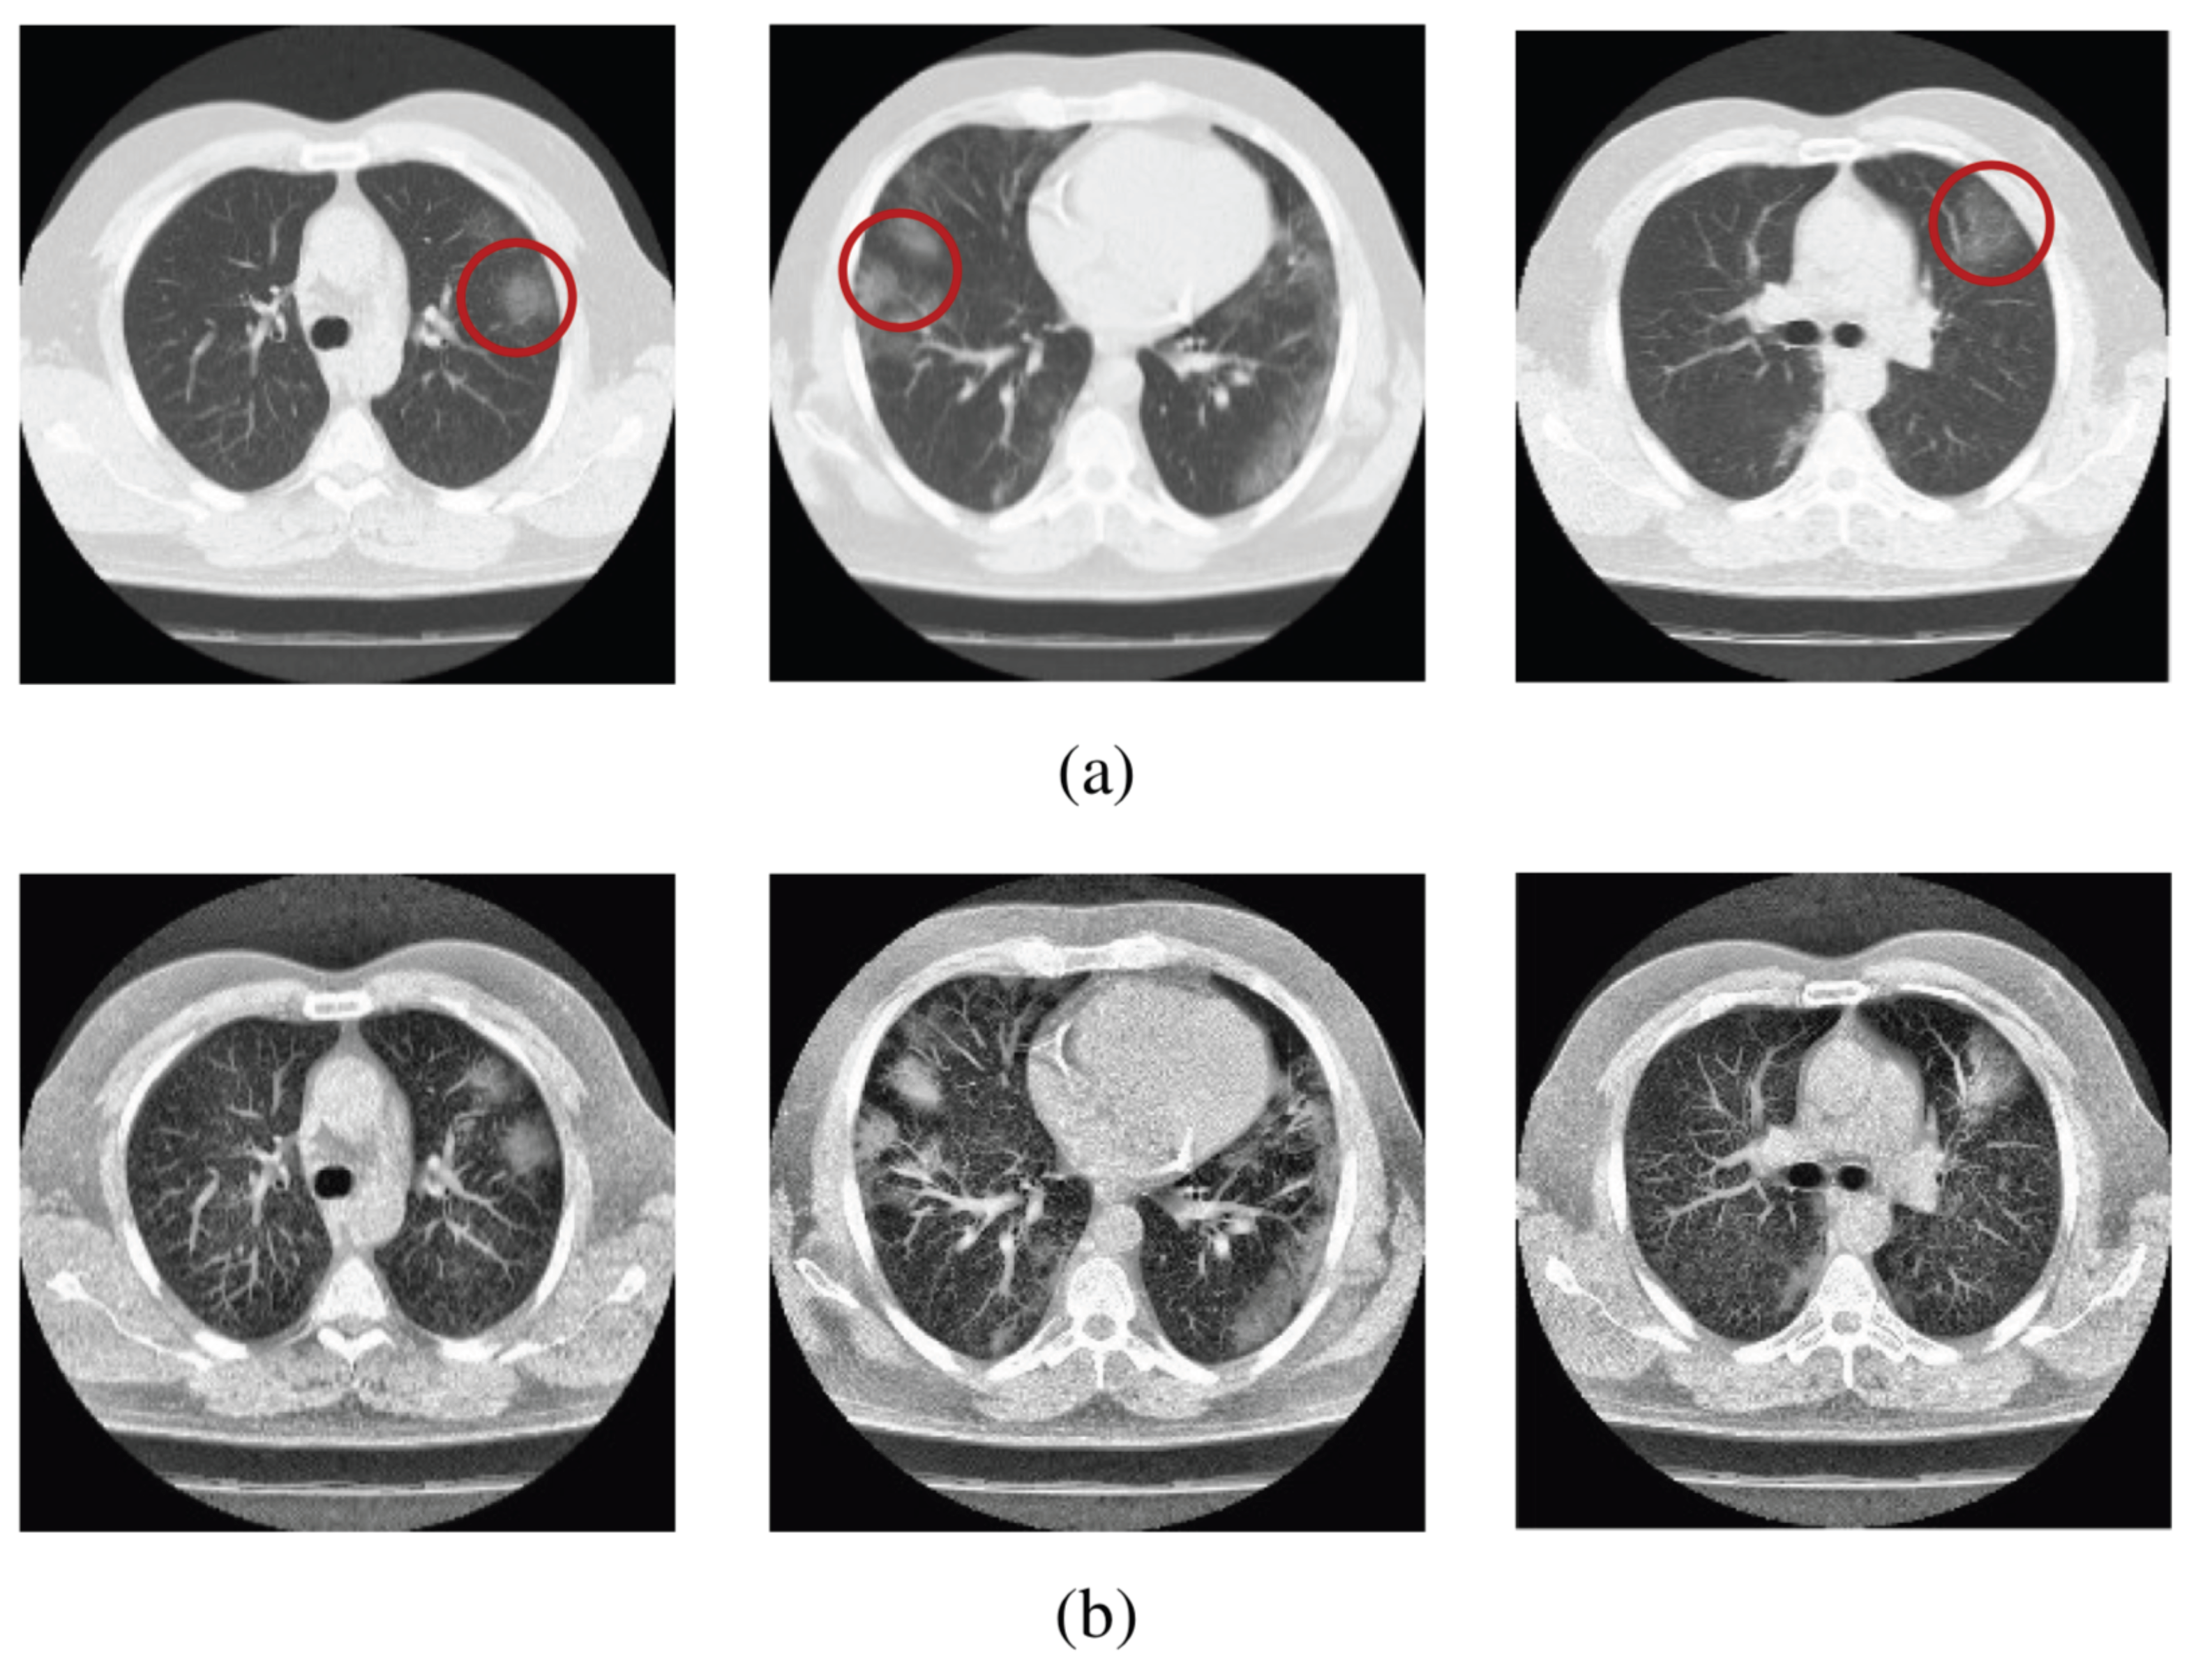

The image of Computer Tomography scans revealing fibrosis due to COVID-19 can be sensibly improved by incorporating in the algorithm the q-entropy with [138], see Figure 27.

Figure 27.

Sample scans from the dataset before and after enhancement showing infected lungs. (a) Original Computer Tomography scans, with red circles highlighting some regions where fibrosis can be seen; (b) enhanced Computer Tomography scans using . From [138].